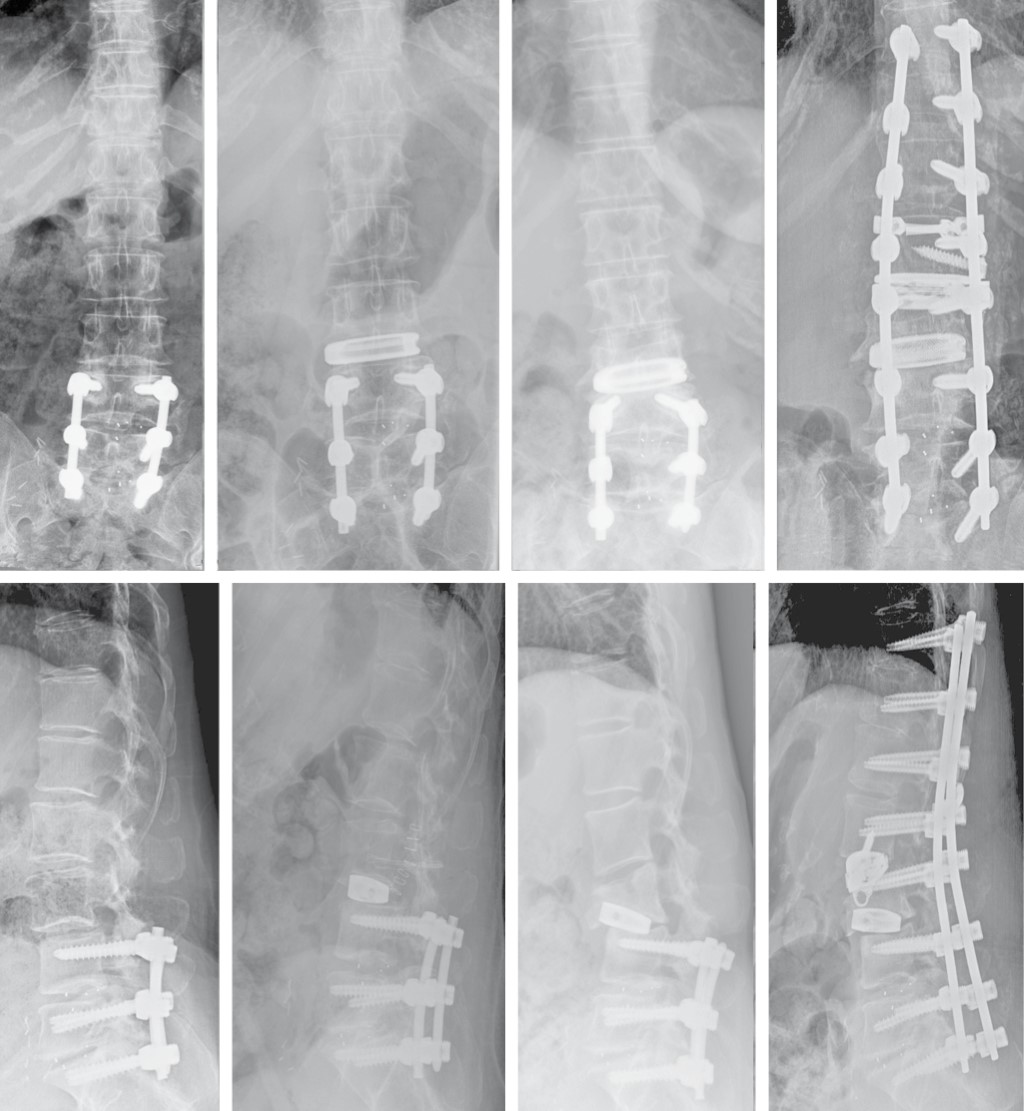

Como complicaciones tardías locales mayores, cabe señalar que no se encontró ningún caso de fístula de líquido cefalorraquídeo o seudomeningocele, ninguna fibrosis perirradicular, hernia abdominal ni infección. Pero se recogieron dos casos de fractura vertebral, una recidiva clínica y una movilización de caja, sin encontrarse diferencias estadísticas entre los grupos. Fractura L4: paciente varón de 85 años con artrodesis lumbar L4-L5 TLIF, hace años que fue intervenido en Noviembre de 2016 realizándose LLIF L3-L4 (PEEK), presenta fractura de L4 en Enero de 2017 (dos meses postquirúgicos) realizándose mediante abordaje bilateral de Wistle retirada de material TLIF previo y artrodesis con tornillos pediculares L2 a L5 (Figura 4). Fractura L3: Paciente mujer 67 años con artrodesis lumbosacra L4-S1 previa que fue intervenida en julio de 2017 realizándose LLIF L3-L4 (titanio), presenta fractura de L3 en Marzo de 2018 que fue intervenida realizándose en un primer tiempo lateral colocación de caja de corrección hiperlordótica. En un segundo tiempo mediante abordaje posterior, extracción de tornillos y barras y se amplía la artrodesis posterior D11-S1 (Figura 5). Movilización caja: mujer de 48 años con antecedentes de artrodesis L5-S1 se intervino en Julio de 2017 realizándose LLIF L4-L5 (PEEK) mediante técnica stand-alone, a las cinco semanas de la cirugía comenzó con un importante dolor lumbar irradiado a miembro inferior izquierdo. El estudio de imagen demostró una movilización mayor de 10 mm. Como tratamiento quirúrgico se procedió a la retirada de la caja por la misma vía transpsoas y ante la imposibilidad de colocar nuevo implante debido a la rotura parcial de la caja y al alto riesgo de lesionar el nervio femoral se decidió rellenar el espacio intersomático mediante injerto con DBM (Figura 6). Recidiva: paciente varón de 82 años con artrodesis lumbar L4-L5 PLIF, hace años que fue intervenido en Julio de 2017 realizándose LLIF L3-L4 (PEEK), presenta recidiva clínica (dolor lumbar y radicular) en Diciembre de 2017 (cinco meses postquirúrgicos), se realizó mediante abordaje posterior descompresión mediante laminectomía L3. Cuatro pacientes (13.8%) fueron reintervenidos (con retirada del implante (movilización y una fractura) y se añadió cirugía de fijación posterior (con descompresión en el caso de la recidiva). El estudio comparativo de las complicaciones no evidenció diferencias respecto al tipo de caja (p = 0.33) ni con respecto a la necesidad de reintervención (p = 0.624) ni a la de retirada de la caja (p = 0.523) (Tabla 5).

Figura 6